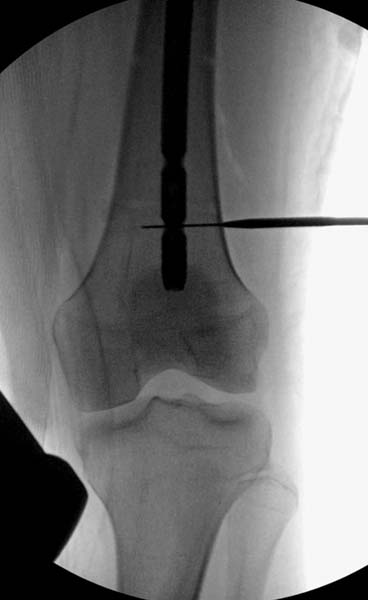

> стабильная.. На третьий день провели стабилизацию перелома бедра

> антеградным остеосинтезом.

> Закрытый БИОС решает множественные проблемы связанные с лечением

> переломов, но проблема дистальной блокировки без рентгена до сих пор